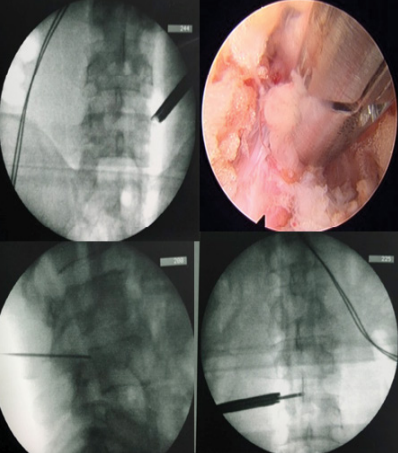

脊椎內視鏡手術-術中影像導引及鏡頭畫面(右上) (圖片來源為世界臨床病例系列雜誌) |

※圖片來源:Lu YM, Yu CH, and Wu HK.(2022). Full Endoscopic Debridement and Drainage for Multilevel Spinal Epidural Abscess: A Case Report and Literature Review. World Journal of Clinical Case Reports and Case Series.